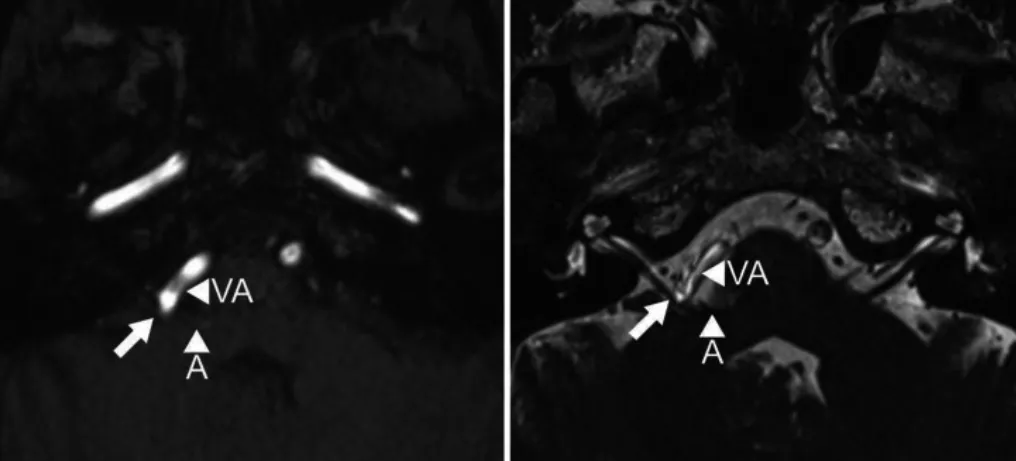

59岁女性患者,患有进行性右侧面肌痉挛2年。曾接受肉毒毒素治疗,但对效果不满意。MRI图像清晰显示小脑前下动脉(AICA)和椎动脉(VA)襻压迫面神经根出脑干区(图1)。

图1:术前MR成像,飞行时间法(左)和稳态构成干涉序列(右)轴位图像显示小脑前下动脉(A)和椎动脉(VA)襻压迫面神经根出脑干区(箭头)。